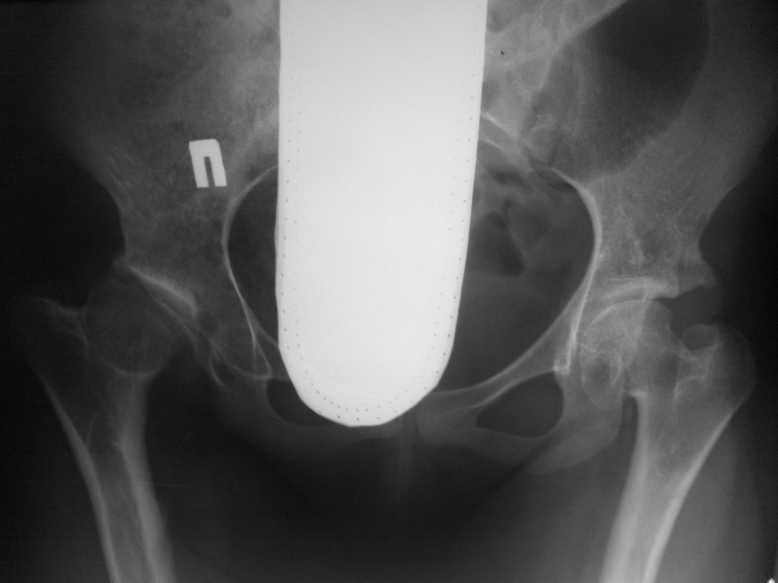

Обратилась девушка 16-ти лет с жалобами на боли в правом тазобедренном суставе

Из анамнеза известно; у пациентки легкая форма ДЦП , в возрасте 5-ти лет ребенок был прооперирован по поводу врожденного вывиха бедер. Клинически ; движения в правом суставе ограничены( сгибание 80,отведение 25, ротация 10-0-5.) Посоветуйте тактику лечения. С уважением Ihor.